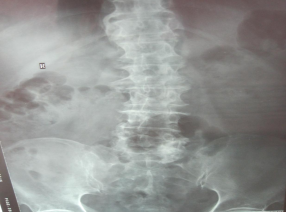

3. 以颈椎和腰椎间盘突出为例

颈腰椎在多种原因的作用下,会在X线片上看到不同程度的骨质增生。但在椎体表面即椎间的上下椎体骨面,尽管破坏严重也未见长出骨刺来。原因很简单,这部分没有任何肌腱韧带附着,也就没有拉力。进而说明骨刺是“拉”出来的。

2.腰椎相关疾病

a.腰部肌肉的劳损;

b.腰椎间盘膨出,突出,腰腿疼痛活动受限;

c.腰椎增生骨化

d.轻度椎管狭窄

e.第三腰椎横突综合征